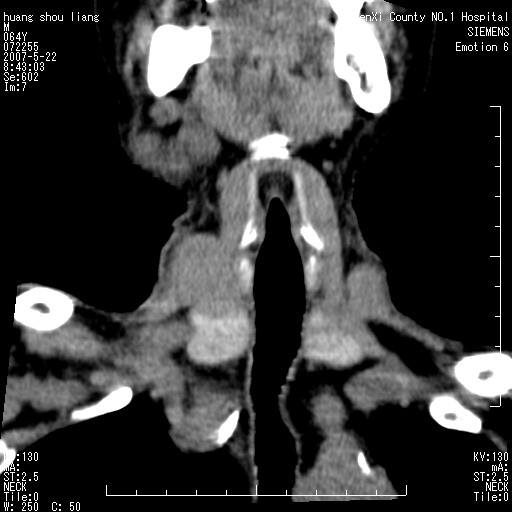

男性,64岁。颈部包块8年。最近增大。

对不起大家,可能是片子发太多有点乱,正常腮腺在下颌角的外侧,颌下腺在下颌体的中部内侧,本例在下颌角内侧偏下,和腺体一点关系都没有,从vrt和mpr上可以很明显看出来,再者肿块是好多粘连在一块的,大家在仔细看看,左侧可能也是吧,我还是考虑为肿大的淋巴结融合在一块,但性质??????

右侧腮腺下部均匀软组织密度肿块,外形不规则,与周围组织分界清晰,考虑右侧腮腺混合瘤或多形性腺瘤。

大家好,病理结果出来了,如大家所说,颌下腺混合瘤。

唉,解剖没学好吧,我诊断错了,不过还是有些不理解回去我在多看看书,谢谢大家的参与,以后我还会奉献好的病例。